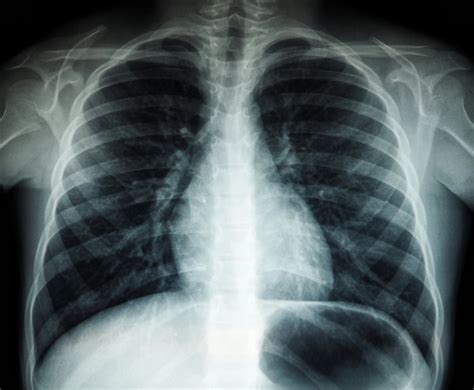

Plaučių uždegimo diagnozė prasideda nuo išsamios medicininės anamnezės ir fizinės apžiūros. Gydytojas klausia apie paciento simptomus, jų trukmę ir stiprumą, taip pat apie galimą kontaktą su infekuotais asmenimis. Pirmiausia gydytojas išsiaiškina, kokie simptomai pasireiškia bei kaip ir kada jie atsirado. Fizinės apžiūros metu stetoskopu klausomi plaučiai, siekiant aptikti būdingus garsus, kurie rodo galimą uždegimą. Klausant (auskultuojant) plaučius tam tikroje jų dalyje, kur prasidėjo galimas plaučių uždegimas, aptinkami karkalai. Įtariant plaučių uždegimą, vizitas pas gydytoją yra būtinas. Namų sąlygomis patvirtinti diagnozės neįmanoma.

Tikslesnei diagnozei nustatyti gali būti atliekami įvairūs laboratoriniai ir instrumentiniai tyrimai:

Atsigavimas po plaučių uždegimo gali būti ilgas procesas. Nors kai kuriems žmonėms sveikata pagerėja per savaitę, kitiems gali prireikti mėnesio ar daugiau, kol jie jausis geriau. Visą mėnesį gali išlikti nuovargis, kosulys, energijos stoka, todėl labai svarbu suteikti kūnui pakankamai laiko atsigauti. Poilsis: Tinkamas poilsis yra ypatingai svarbus visiškam atsigavimui. Reabilitacijos laikotarpiu gali būti rekomenduojami specialūs kvėpavimo pratimai, padedantys atkurti plaučių funkciją. Mityba turi būti pilnavertė, turtinga baltymų ir vitaminų. Būtina vartoti daug skysčių, kad suskystėtų likę skrepliai ir būtų lengviau juos pašalinti. Sveikimo laikotarpiu rekomenduojama vengti didelio fizinio krūvio, tačiau visiškai gulėti lovoje taip pat nepatartina. Lengvas judėjimas, pavyzdžiui, trumpi pasivaikščiojimai gryname ore, skatina plaučių ventiliaciją ir kraujotaką. Specialiai parinktos vitaminų ir mikroelementų lašelinės gali padėti greičiau atsigauti po plaučių uždegimo, sustiprinti imuninę sistemą ir sumažinti ligos komplikacijų tikimybę. Galiausiai, nepamirškite pakartotinio vizito pas gydytoją. Paprastai po gydymo kurso (praėjus apie mėnesiui) rekomenduojama pakartoti rentgeno tyrimą, kad būtų įsitikinta, jog plaučiuose neliko uždegiminių pakitimų ir infekcija visiškai įveikta.